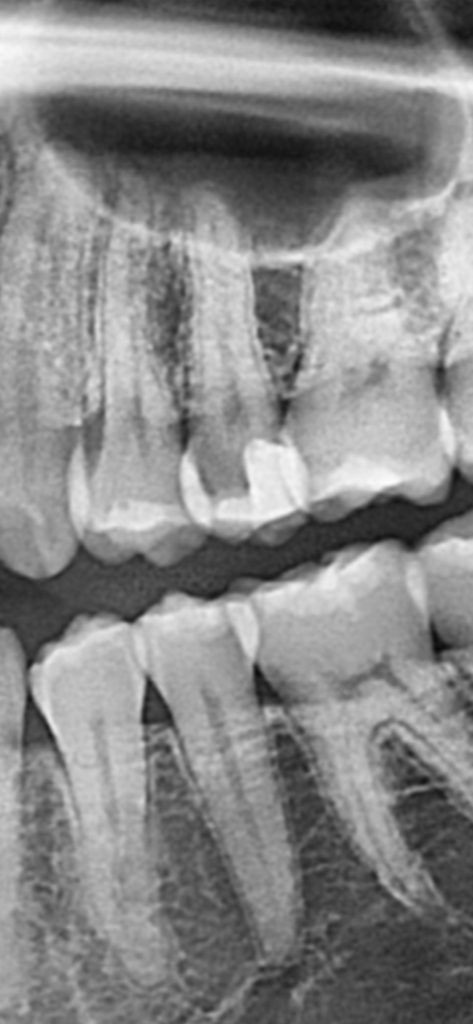

방사선사진으로만 본다면 아래치아는 충치의 가능성이 높습니다.

위의 치아는 충치일수도 있고, 단순히 방사선흑화도가 높아서 그렇게 보이는것일수도 있습니다

정확한 판단을 위해선 눈으로 직접 검사를 해봐야 알 수 있을 것으로 보입니다. 감사합니다.

말씀하신 부위 모두 충치입니다. 방사선 사진을 촬영할 때, tearing 된 부위도 비슷하게 보이나 현재 치아가 겹쳐져 있는 상태에서 지금과 같은 정도의 radiolucency를 보인다면 이는 충치일 가능성이 매우 높습니다. 따라서 치료를 해야할 것으로 보이며 신경과도 어느정도 근접하므로 신경치료의 가능성도 열어두셔야 합니다.

사진상으로 보이는 부분은 충치는 아닌거 같습니다. 일종의 파노라마 사진의 오류일꺼 같습니다. 정확한건 눈으로 직접보거나 작은 사진을 찍어보면 알수 있습니다.